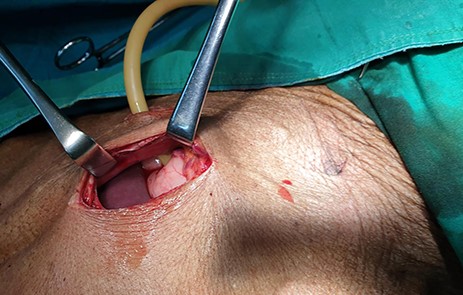

The patient was scheduled for GFT insertion. Under aseptic technique, with the patient in supine position, 24 Fr urinary catheter as an improvised GFT was inserted in Stamm manner, haemostasis achieved, abdomen closed in layers and dressed (Fig. 9). There was no ascites and mesenteric lymph nodes were not palpable. After the procedure the patient was discharged home on the second day with analgesics and was booked for a surgical outpatient clinic appointment after 2 weeks.

24Fr urinary catheter as an improvised gastrostomy feeding tube.